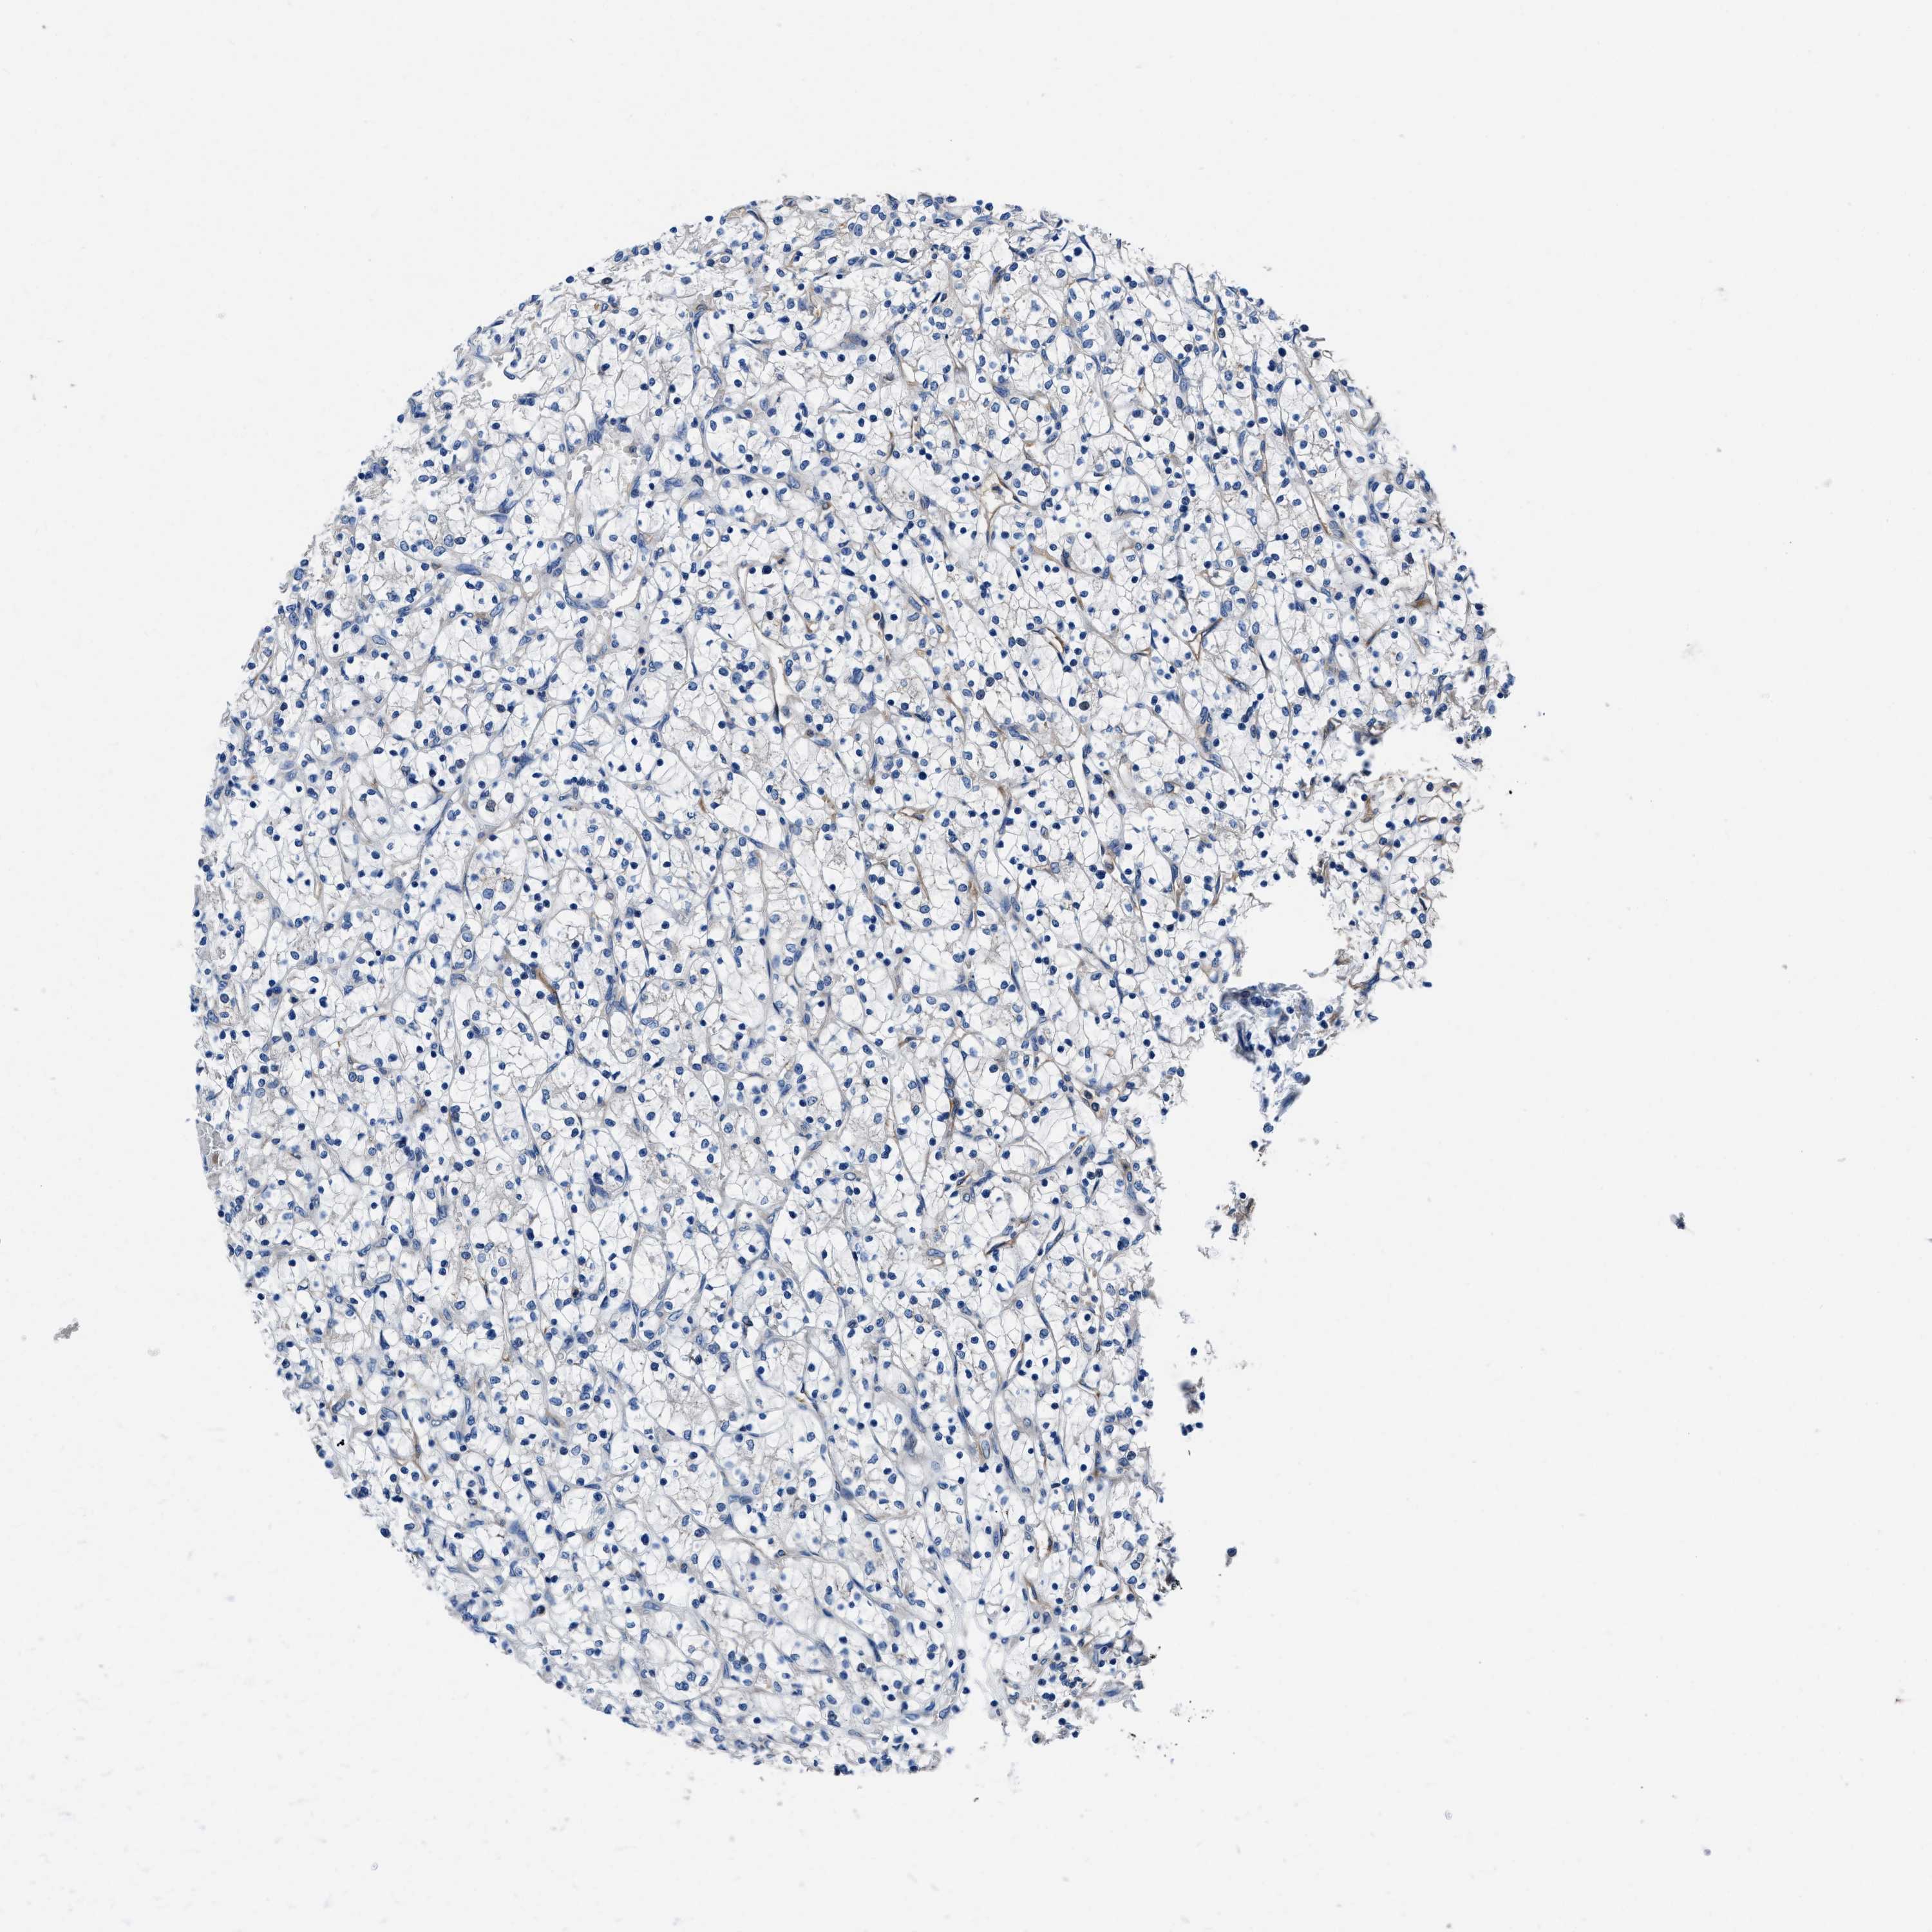

KIDNEY RENAL CLEAR CELL CARCINOMA (TCGA) - Interactive survival scatter ploti

The Survival Scatter plot shows the clinical status (i.e. dead or alive) for all individuals in the patient cohort, based on the same data that underlies the corresponding Kaplan-Meier plots. Patients that are alive at last time for follow-up are shown in blue and patients who have died during the study are shown in red.

The x-axis shows the expression levels (FPKM) of the investigated gene in the tumor tissue at the time of diagnosis. The y-axis shows the follow-up time after diagnosis (years). Both axes are complimented with kernel density curves demonstrating the data density over the axes. The top density plot shows the expression levels (FPKM) distribution among dead (red) and alive patients (blue). The right density plot shows the data density of the survived years of dead patients with high and low expression levels respectively, stratified using the cutoff indicated by the vertical dashed line through the Survival Scatter plot. This cutoff is automatically defined based on the FPKM cutoff that minimizes the p-score. The cutoff can be changed by dragging the vertical line or by entering a cutoff value in the square labeled "Current cut-off".

Under the Survival Scatter plot the p-score landscape (black curve; left axis) is shown together with dead median separation (red curve; right axis). Dead median separation is the difference in median mRNA expression between patients who have died with high and low expression, respectively. It is calculated as follows: median FPKM expression of dead patients with high expression - median FPKM expression of dead patients with low expression. This is intended to aid the user in visually exploring custom cutoffs and the associated p-scores and dead median separation.

Individual patient data is displayed and can be filtered by clicking on one or more of the category buttons on the top of the page. Categories describing expression level and patient information include: high, low, alive, dead, female, male and tumor stages. The scale of the x-axis can be toggled between linear and log-scale by clicking on the "x log" button. Mouse-over function shows TCGA ID, patient information and mRNA expression (FPKM) for each patient.

& Survival analysisi

Kaplan-Meier plots summarize results from analysis of correlation between mRNA expression level and patient survival. Patients were divided based on level of expression into one of the two groups "low" (under cut off) or "high" (over cut off). X-axis shows time for survival (years) and y-axis shows the probability of survival, where 1.0 corresponds to 100 percent.

NEU1 is potential prognostic, high expression is favorable in Kidney Renal Clear Cell Carcinoma (TCGA)

Best expression cut offi

Based on the FPKM value of each gene, patients were classified into two groups and association between prognosis (survival) and gene expression (FPKM) was examined. The best expression cut-off refers the FPKM value that yields maximal difference with regard to survival between the two groups at the lowest log-rank P-value. Best expression cut-off was selected based on survival analysis .

When clicking on this number, the vertical dashed line indicating cut-off, the interactive survival plot, and the Kaplan-Meier curve will be adjusted to show results based on the best expression cut-off.

: 1.86

TCGA RNA samplesi

RNA-seq data is reported as average FPKM (number Fragments Per Kilobase of exon per Million reads), generated by the The Cancer Genome Atlas (TCGA) .

Normal distribution across the dataset is visualized with box plots, shown as median and 25th and 75th percentiles. Points are displayed as outliers if they are above or below 1.5 times the interquartile range. FPKM values of the individual samples are presented next to the box plot.

Average pTPM 1.3

Number of samples 521